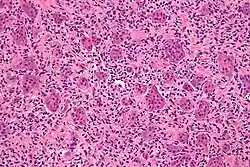

Micrograph of a giant-cell tumor of bone showing the characteristic giant cells, H&E stain

The diagnosis of giant-cell tumors is based on biopsy findings. The key histomorphologic feature is, as the name of the entity suggests, (multinucleated) giant cells with up to a hundred nuclei that have prominent nucleoli. Surrounding mononuclear and small multinucleated cells have nuclei similar to those in the giant cells; this distinguishes the lesion from other osteogenic lesions which commonly have (benign) osteoclast-type giant cells. Soap-bubble appearance is a characteristic feature.